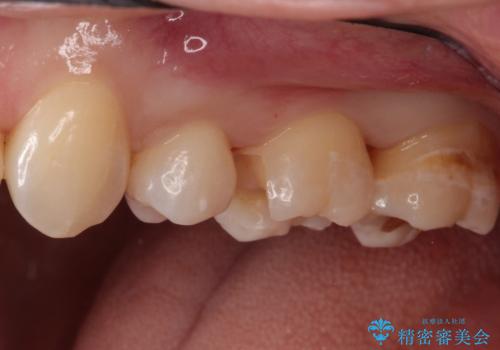

- 他院で虫歯になっていると指摘され来院されました。適合の良いゴールドインレーによる治療がされていましたが、違う部分が虫歯になってしまっていました。審美性の良いセラミックインレーを希望されました。

ゴールドインレーを除去し、その下で広がっていた虫歯をきれいに取り除きました。